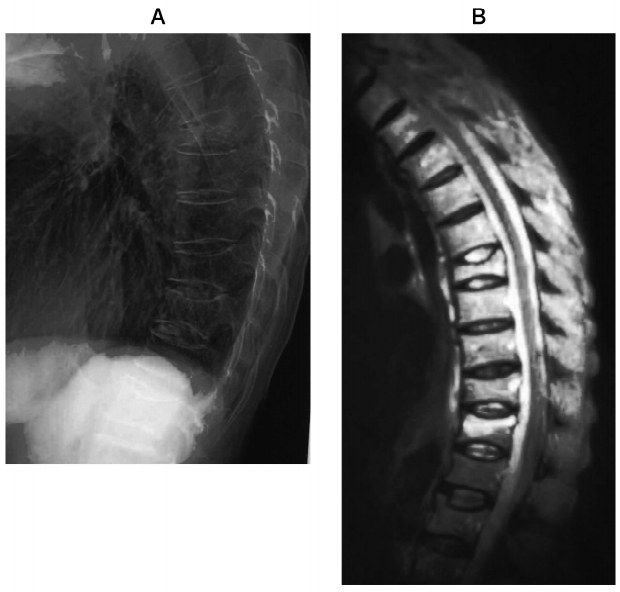

78歳の女性。布団を持ち上げようとした際、背部から腹部への強い帯状痛を生じ、寝返りも困難となったため入院となった。入院時のエックス線写真(図A)と MRI(図B)とを別に示す。

この患者の病態はどれか。2つ選べ。